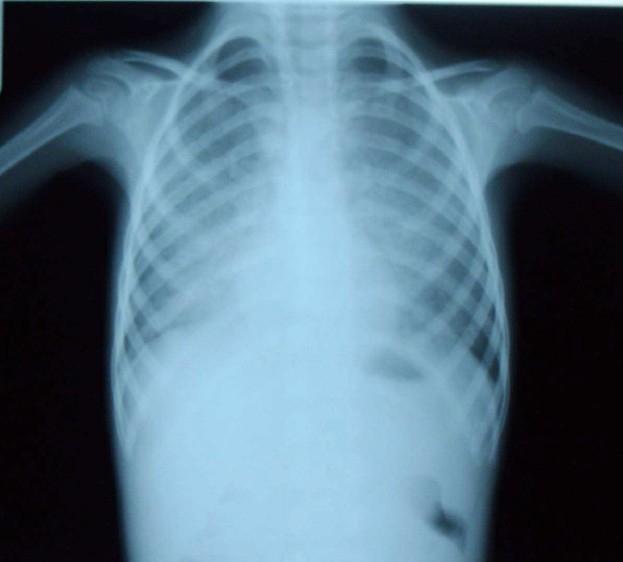

Pulmonary alveolar proteinosis, (PAP) is a rare disease of unknown etiology, characterized by accumulation of intraalveolar proteinaceous material which is rich in lipid and positive on periodic acid-Schiff stain. Two clinically different pediatric types have been defined as congenital PAP which is fulminant and fatal, and a late-onset PAP which is similar to the adult form and less severe. Eight children with late-onset PAP were hospitalized from 1998 to 2005 in Mofid Children Hospital. Characteristics of these patients and the methods of diagnosis and treatment are presented in this case series.

肺泡蛋白沉积症(PAP)是一种病因不明的罕见疾病,其特征是肺泡内富含脂质的蛋白质物质积聚,且过碘酸-希夫染色呈阳性。临床上已定义了两种不同的儿科类型,即暴发性且致命的先天性PAP,以及与成人形式相似且病情较轻的迟发性PAP。1998年至2005年期间,8名迟发性PAP患儿在莫菲德儿童医院住院。本病例系列介绍了这些患者的特征以及诊断和治疗方法。